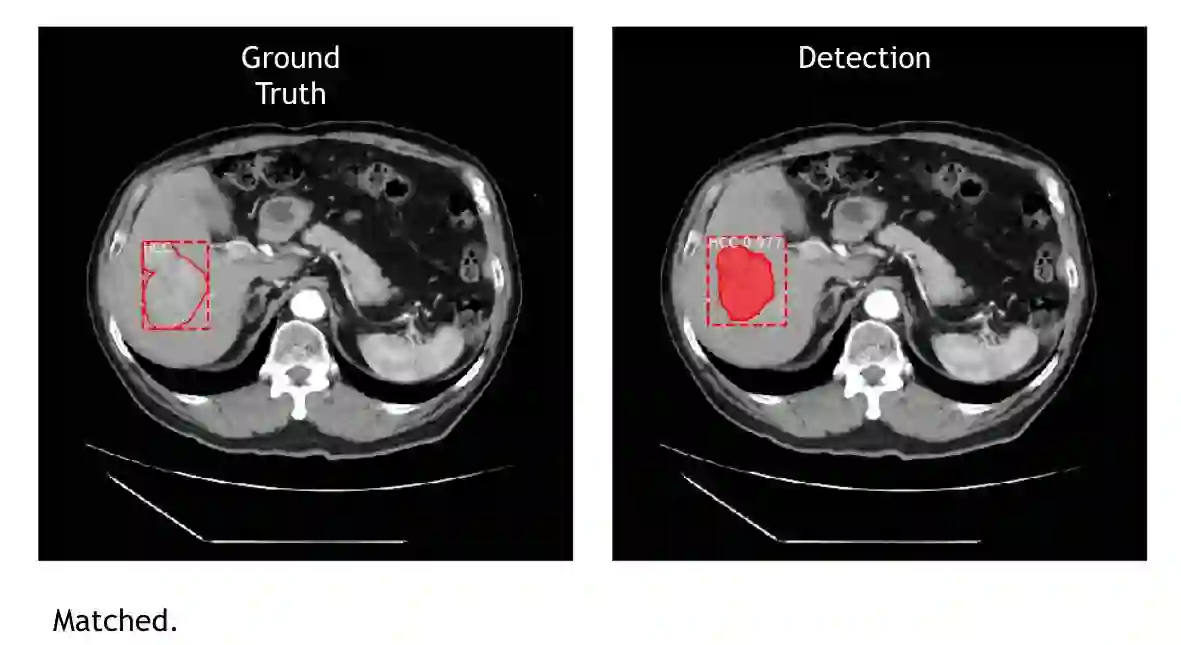

先用下方的肝脏 CT 图片来解释,左边 Ground Truth 图是传统的做法,就是医生看片子,把肿瘤的位置、大小框出来。右边 Detection 图是 AI 侦测的结果,上头显示 HCC(肝细胞癌 Hepatocellular Carcinoma,简称HCC) 0.977 ,数字指的是机器下判断的自信程度(与准确率无关,只是机器在做判断时对答案的自我评估)。

图|左图是医生手动标示,右图是 AI 侦测的结果,HCC 0.977 数字是机器下判断的自信程度。(图片来源:CMUH人工智能医学诊断中心